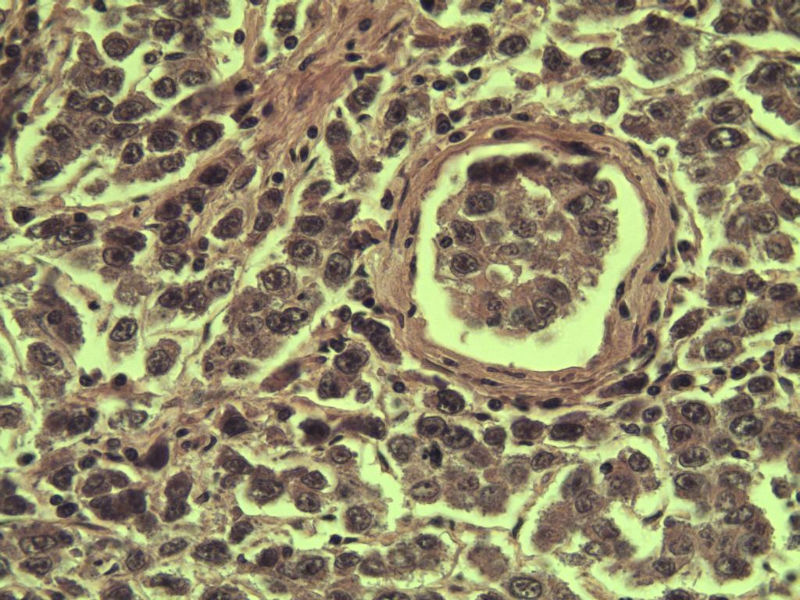

男 27岁 腹腔隐睾 5*3*2 cm, 切面灰红灰黄、实性、质中,请各位老师看看,是精原细胞瘤吗?感觉不像.腹腔隐睾图1

名称:图1

描述:a207.Jpg.jpg